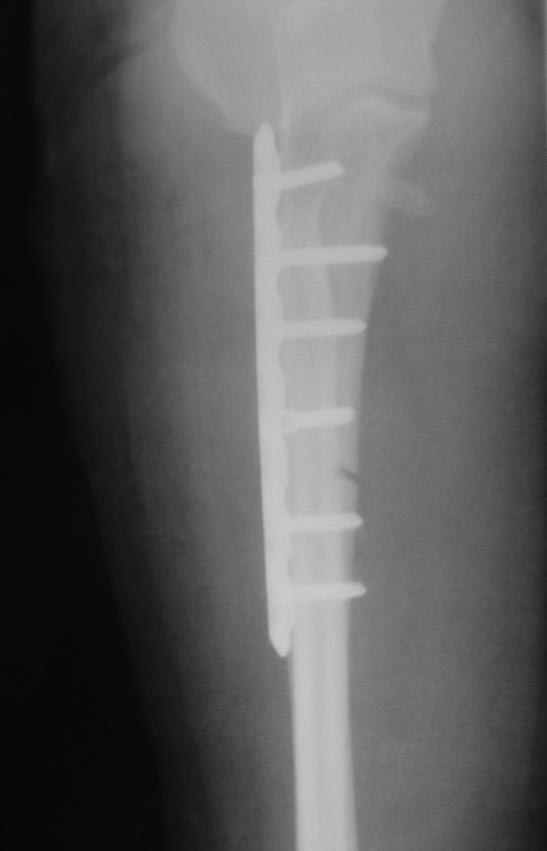

Хочу попросить совета у сообщества по поводу следующего клинического случая. Женщина, 65 лет. Закрытый перелом Монтеджи слева в октябре 2013 года. (рис. 1, 2). Для наглядности сделал скиаграмму перелома (рис. 3, 4). На 8-е сутки накостный остеосинтез пластинами с угловой стабильностью. Головка луча была восстановлена из отломков (рис. 5) и собрана на спицах одну из которых скусили и оставили под пластиной.(рис. 6). Вроде получилось стабильно, видео на операции по этой ссылке:

http://youtu.be/vdeYGTWrTmkНа рентгенограмме тоже вроде ничего. (рис. 7, 8).Из реабилитации порекомендовали заниматься с первого дня движениями в суставе (пронация/супинация, сгибание/разгибание), выполнять несложную домашнюю работу. Видео объма движения на 7-е сутки после операции по ссылке: http://youtu.be/KyPAUmEIhs4